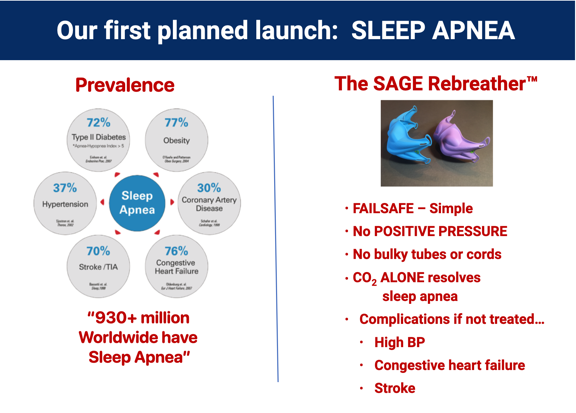

Sleep Apnea

So, what is the underlying problem? LOW CO2 appears as the common irregularity among the conditions above; another 15+ conditions show the same underlying cause. The solution clearly requires a means of elevating the body's CO2 level safely, conveniently, and inexpensively. From reviewing existing Sleep Apnea research and from several of our own lab studies, we believe the single solution for multiple adverse health conditions lies with elevating the body's CO2 level. DrDave™ Smith found a clever way to accomplish this while meeting the specified requirements: The SAGE Rebreather™ mask. And here's how it works...

Our SAGE Rebreather opens the door for making life better for millions. Our platform technology appears to be able to overcome 15+ adverse human conditions measuring in excess of 2 billion people worldwide. Here are the numbers we've been able to find for just the first three use-cases...